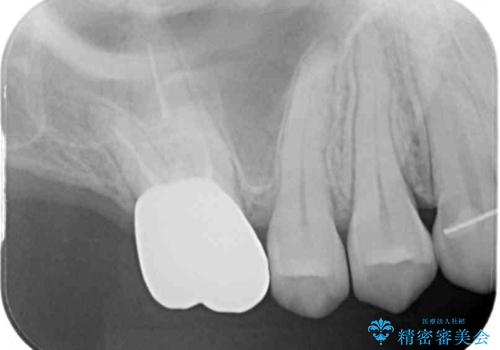

- 前歯の隙間と奥歯の目立つ銀歯を気にして来院された患者様です。

インビザラインにより下顎前歯の隙間を閉じるとともに、奥歯の咬み合わせを改善させることとしました。

矯正治療後には、銀歯のクラウンをセラミッククラウンへ替える補綴治療を行うこととしました。

左右奥歯の咬み合わせを変更させる必要があったため、治療期間は長くなることが予想されました。

1日22時間以上の装着時間をしっかりと守ってくださったので、順調に治療を進めることができました。